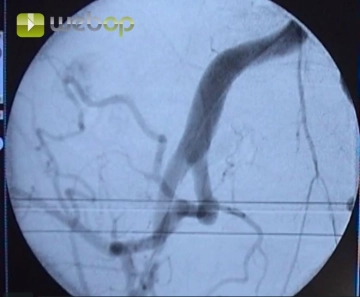

Consejo:

Evitar en lo posible la punción a la altura del ligamento inguinal o superior, porque con ello aumenta el riesgo de hemorragia posterior debido a una compresión postprocedimental deficiente de la arteria.